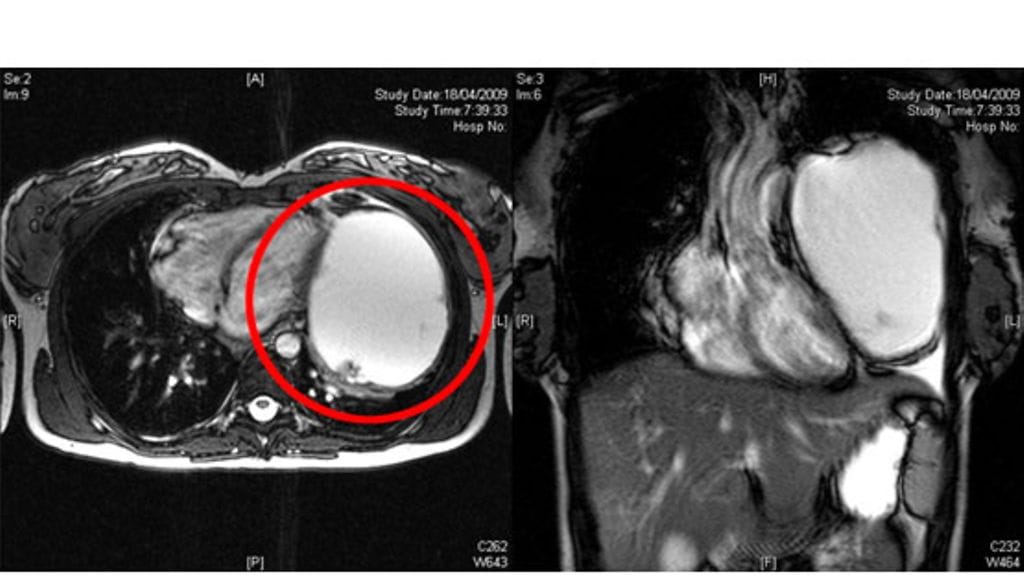

Kun Nicola oli 13. raskausviikolla, äidin rinnassa ollut kasvain oli jo vesimelonin kokoinen. Lääkärit päättivät poistaa epämuodostumakasvaimen, sillä muutoin äiti ja vauva olisivat menehtyneet.

Hän oli kuitenkin päättänyt selvittää kipujensa syyn ja kääntyi sydänlääkärin puoleen. Magneettikuvaukset paljastivat valtaisan, jo keuhkojen suuruisen kasvaimen rinnassa.

Kirurgit eivät voineet leikata Nicolaa heti, kun kasvain huomattiin, sillä hänen vauvansa kehitys oli niin herkässä vaiheessa. Koska hirviökasvain kuitenkin kasvoi ja esti jo vauvan hapensaannin, oli leikkausta pakko kiirehtiä. Kesällä 2009 kirurgit tekivät leikkauspäätöksen ja ahkeroivat kahden tunnin ajan pelastaakseen kaksi elämää.